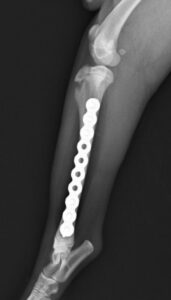

落下事故で右足の脛を骨折したワンちゃんが来院されました。ロッキングプレートであるMATRIX2.5と2.4スクリューで手術し、無事元気に歩いて退院していきました。よかったね。